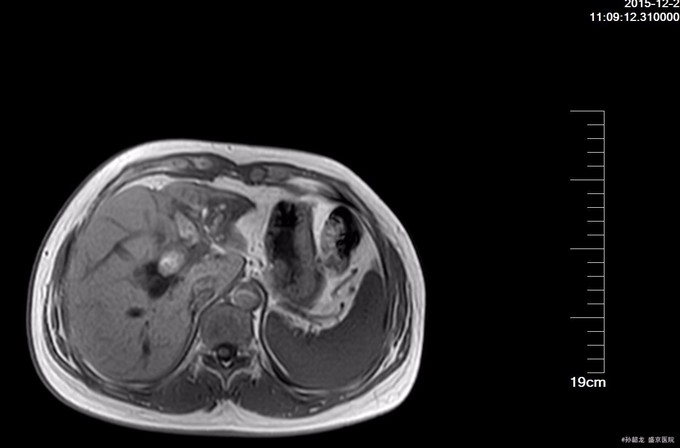

查体:全身皮肤及巩膜无黄染,腹软不胀,未见胃肠型及蠕动波,全腹平软,全腹无压痛及无反跳痛,无肌紧张,Murphy's征(-),肝区叩痛(-),双肾区叩击痛(-),移动性浊音(-),肠鸣音6次/分。 辅查: 肝功能化验,总胆红素及直接胆红素正常,转氨酶有升高。 MRCP提示胆囊增大,肝内外胆道内多发结石,伴胆道梗阻。 腹部BUS提示 1.肝外胆道梗阻, 2.肝门部胆管至胆总管内结石, 3.肝内胆管结石。

诊断: 肝内外胆管结石 治疗:全麻下手术探查:胆囊约10*3.0*3.0cm,壁厚约0.3cm,与周围组织粘连,胆总管扩张,直径3cm,内可触及结石,肝脏左叶萎缩,内及结石,术中诊断胆囊炎 ,胆总管结石,左肝萎缩,左肝内胆管结石,行胆囊切除,左半肝切除, 胆总管切开取石 ,T 管引流术。术后病理证实(左半)肝内胆管结石,伴慢性炎症,慢性胆囊炎。